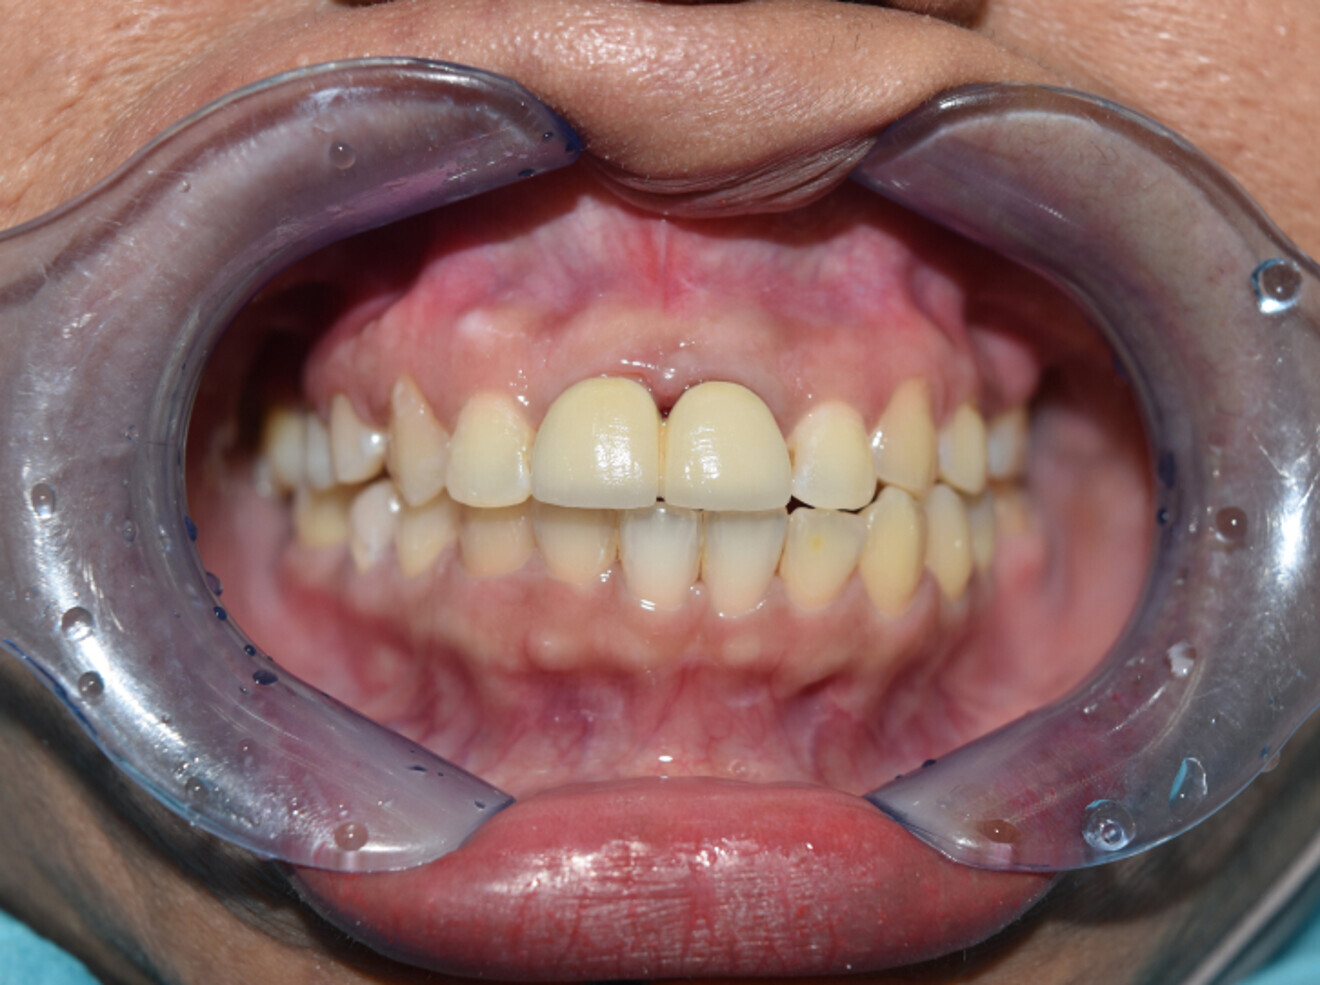

Case 1

• 64-year-old woman

• No underlying medical condition.

• Main complaint: Mobile upper front teeth. Big gap between upper centrals.

Intra-oral findings:

Class I malocclusion with poli diastemas in the upper anterior region.

Overbite= 2mm, Overjet= 2mm.

No molar classification (absence of molars).

Class I canine on right and left side.

Upper midline (mesial to 11) on with face.

Lower midline on with the chin.